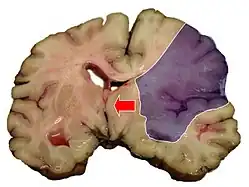

Ишемический инфаркт является самым частым проявлением (75 % случаев) ишемического инсульта. Он выглядит как очаг серого размягчения ткани мозга. При микроскопическом исследовании среди некротизированных масс находят погибшие нейроны[28]:360.

Геморрагический инфаркт мозга внешне похож на очаг геморрагического инсульта, однако имеет другой механизм возникновения. Первично возникает ишемия головного мозга; вторично — кровоизлияние в ишемизированную ткань. Геморрагический инфаркт чаще встречается в коре мозга, реже — в подкорковых узлах[28]:360.

При смешанном инфаркте, который всегда возникает в сером веществе мозга, можно найти участки как ишемического, так и геморрагического инфакта[28]:360.